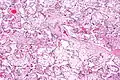

Placental villous immaturity

Placental villous immaturity is chorionic villous development that is inappropriate for the gestational age.

| Micrograph of villous immaturity. H&E stain. | |

Immature chorionic villi are larger and have more central blood vessels; thus, the diffusion distance for gas and nutrient exchange is larger and, therefore, placental function is impaired.